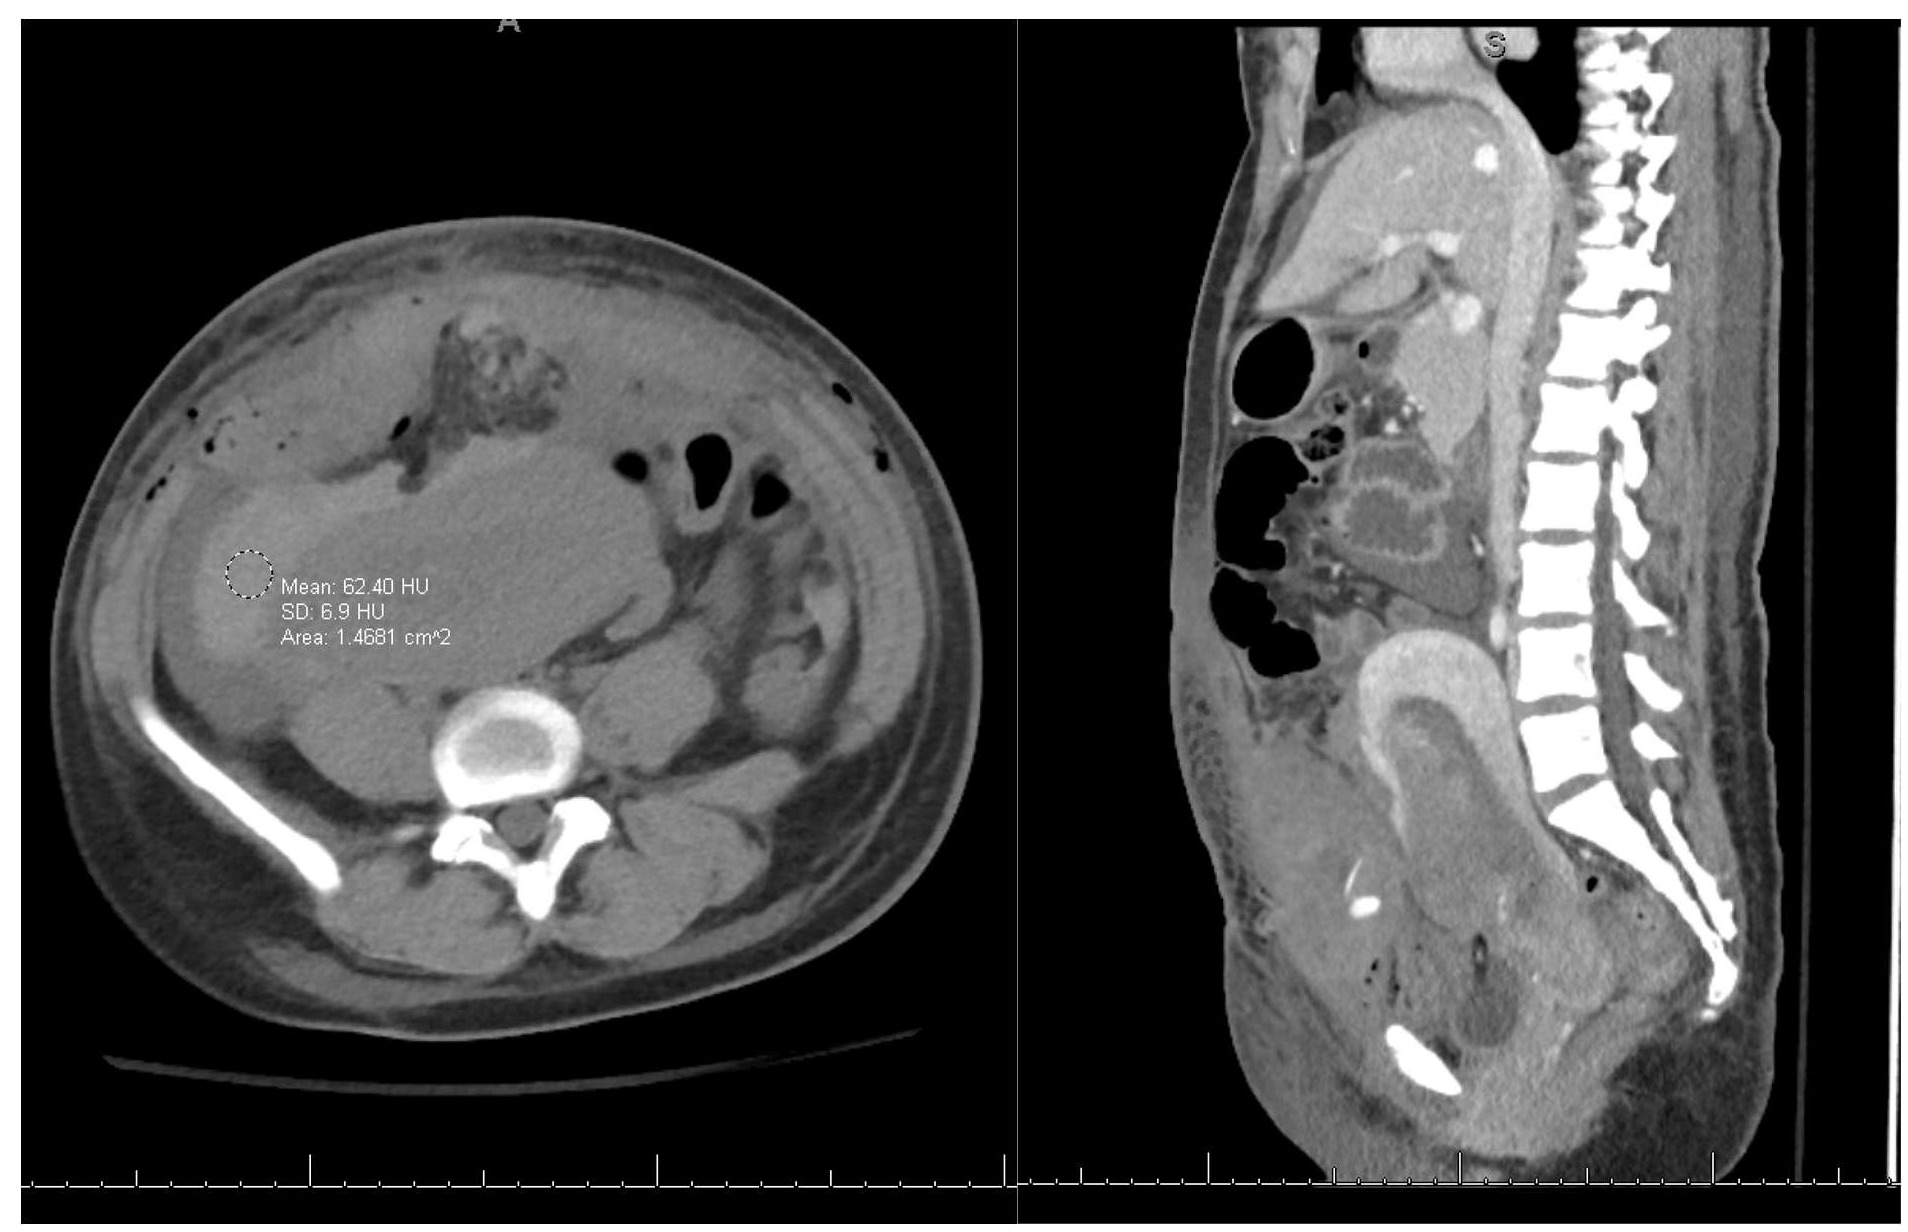

Shortly after transferring the patient to the recovery area, active bleeding was noted at the surgical site, saturating the dressing. Frank red blood was seen in the JP drain. Interventional radiology was consulted to evaluate for possible intravascular embolization. Multiple sites of both the left and right inferior epigastric arteries were identified as sources of active bleeding on CT angiography. Successful coil embolization of bilateral inferior epigastric arteries was performed. Figure 2 demonstrates active extravasation of contrast prior to embolization in comparison to post embolization arteriograms. She received a total of three units of packed red blood cells with and estimated total blood loss of 2000 cc. Despite these losses, the patient remained hemodynamically stable with a normal coagulation profile. The JP drain was removed prior to discharge.